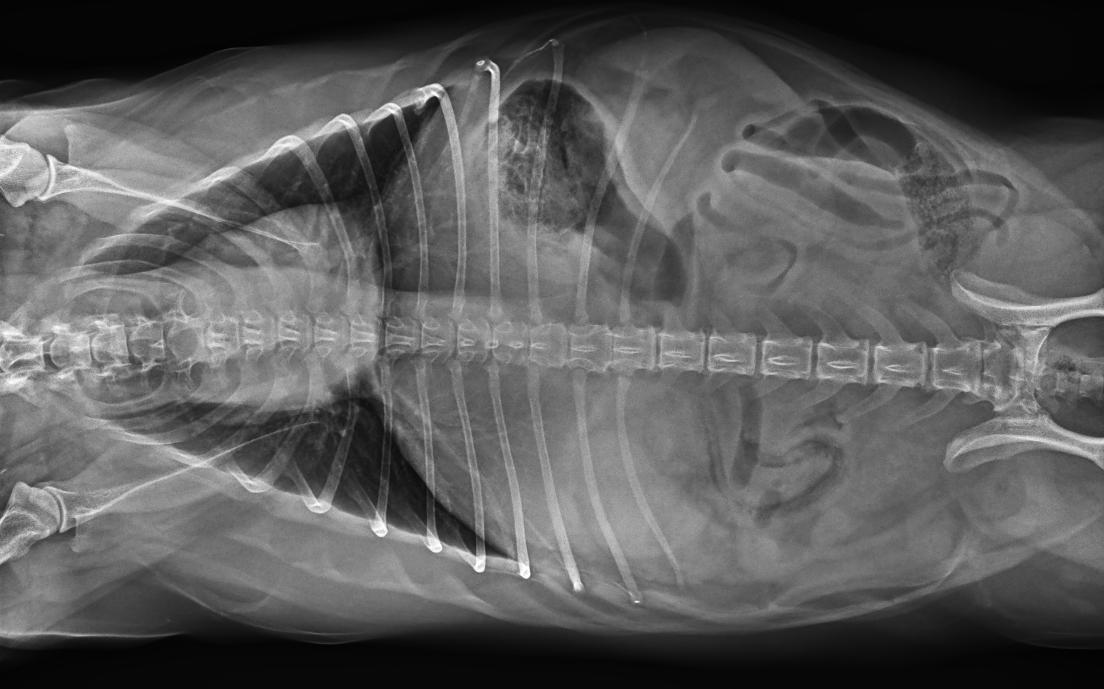

● 17*17大尺寸平板探測器,獲得高質量圖像

● 優(yōu)異的空間分辨率及信噪比,提升圖像質量

● 采用線噪聲消除技術,使成像質量提升40%

● 智能高效的圖像處理軟件,大幅提升圖像質量